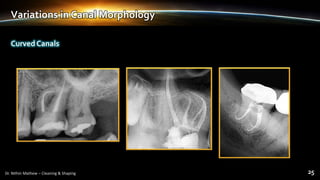

Curved Canals

Variations in Canal Morphology